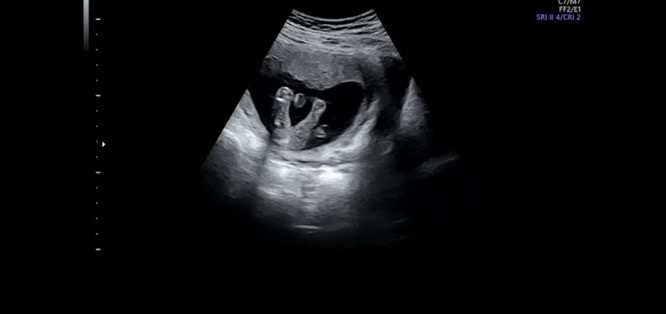

16주, 반전없겟죠?

병원에서는 딸이라고 하는데, 반전 없겟죠?